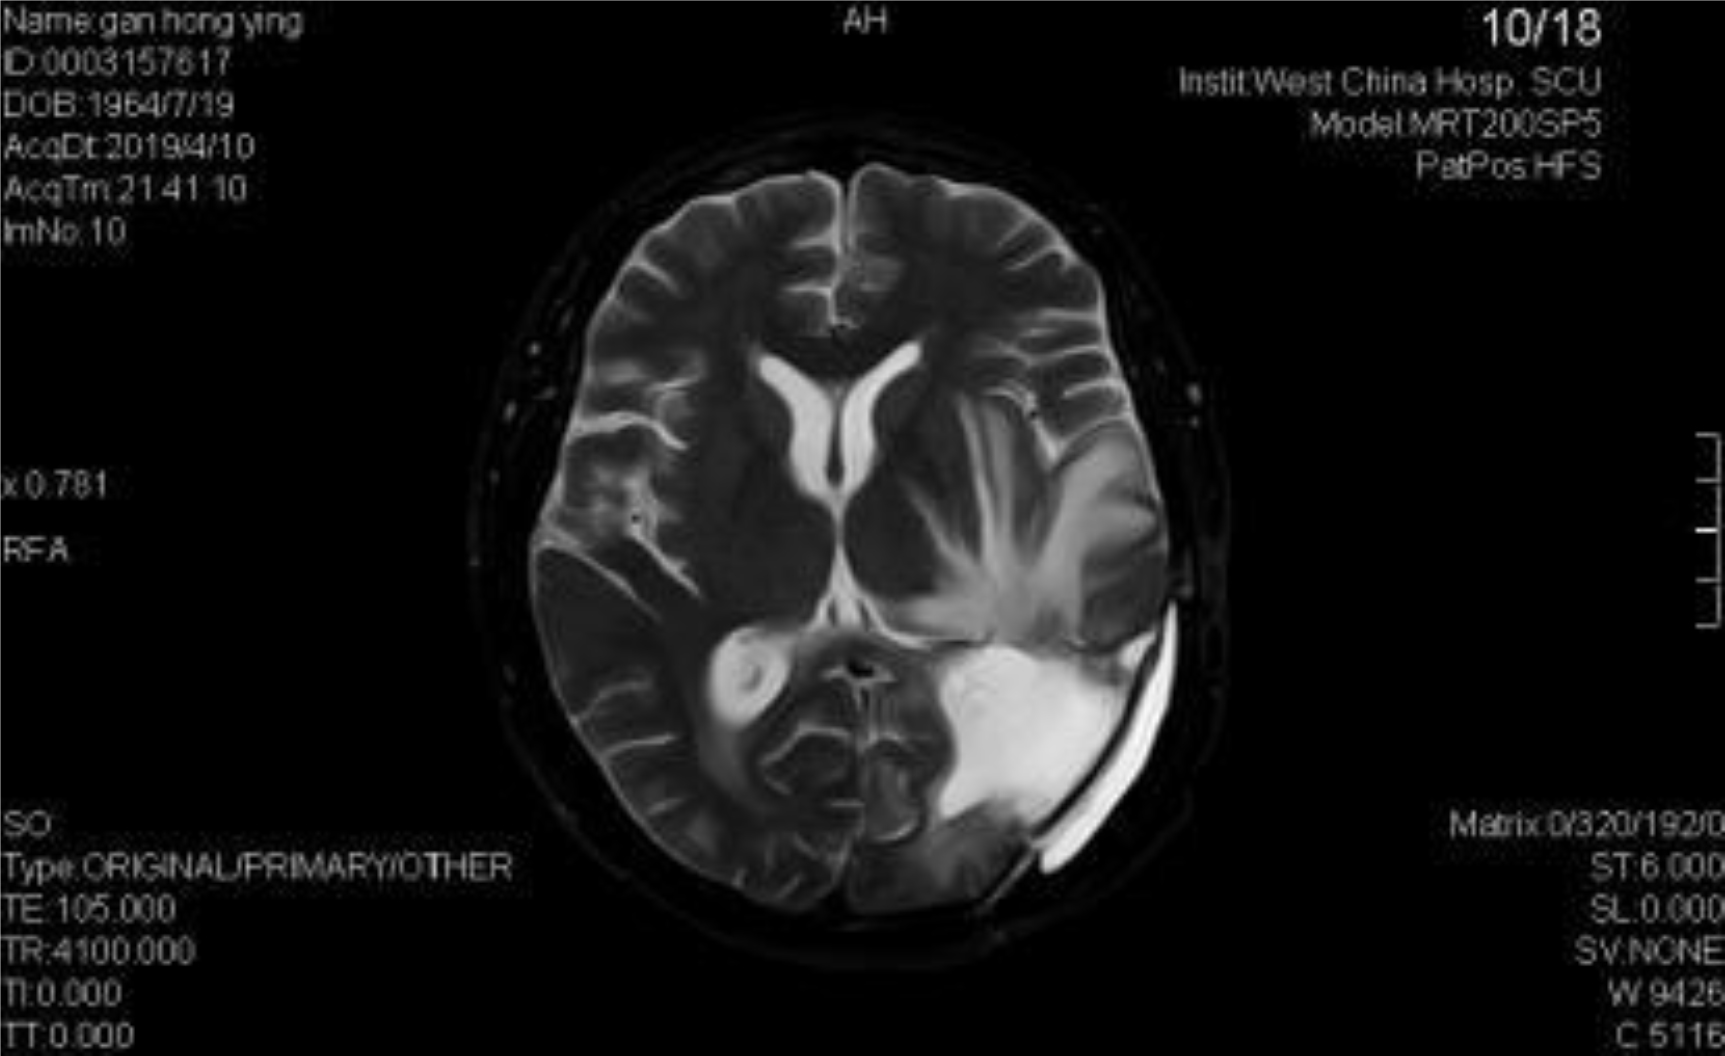

A 54-year-old female, developed a headache in December 2017. Examination showed that the left parietal occipital lobe occupied, and the first surgical treatment was performed, and the postoperative pathological diagnosis was glioblastoma. After operation, the patient received routine radiotherapy, 60Gy/33f, and temozolomide chemotherapy, 100mg/d (during radiotherapy), 300mg d1-5, q4w. In January 2019, the patient reexamined the MRI and found that the left temporal parietal space was occupied (Figure 1) and was operated again. The postoperative pathological diagnosis was still glioblastoma. The patient had occasional headache after operation, and the head MRI examination three months after operation indicated the progress of the disease (Figure 2). TTF was prepared to be used, and finally officially used the TTF treatment on July 4, 2019. The use time was relatively fixed, the utilization rate was 93%, and the compliance was good (Figure 3). During treatment, the patient developed allergic rash scattered on the scalp, mild itching, no ulceration and infection, and recovered quickly after topical application of antiallergic drugs. There had been several times that the patch temperature was too high, and the reasons are as follows: 1. The ambient temperature used was high (e. G. hot weather, direct sunlight, etc.). 2. The contact between the patch and the skin was not good. By instructing the patient to adjust the indoor temperature to about 24 °C, to use the headband or tape to strengthen the loose patch, to use the headband when sleeping at night, and to pay attention to clean the hair of the scalp every time, the situations had been significantly improved. Re-examination of the MRI in October 2019 showed that the condition was stable (Figure 4). Follow-up to 2020.1.23, the patient showed no symptoms of discomfort.

Figure 2